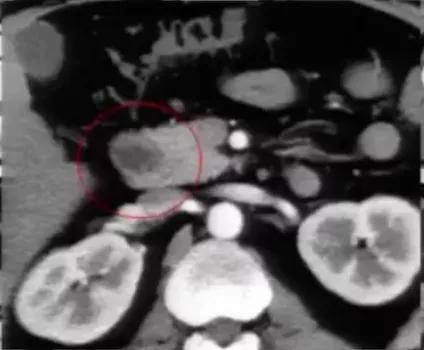

肾癌伴血管结构畸形

肾癌伴血管结构畸形患者的血管结构畸形往往容易被忽视。 在手术的过程中,如不注意就可能造成肝右叶血流的回流障碍,导致严重的临床后果。